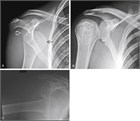

Shoulder dislocations occur as a result of trauma or from minimal movements such as reaching backward. They most often dislocate anteriorly, resulting in a squared-off deformity of the lateral shoulder and decreased range of motion at the shoulder. There are many techniques used to perform reduction, and clinicians should be comfortable with several of them. Reduction can generally be accomplished without analgesia, but difficult reductions may require procedural sedation and analgesia. Post-reduction, patients should be placed in a sling for comfort with instructions to avoid the activities and movements that caused the dislocation, to gently mobilize the shoulder and elbow early. Close orthopedic follow-up should be provided.